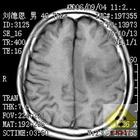

膠質母細胞瘤細胞膠質母細胞瘤在神經上皮性腫瘤中占22.3%,有報告占顱內腫瘤的10.2%。僅次於星形細胞瘤而後第2位。本病主要發生於成人,尤其30一50歲多見,男性明顯多於女性,約2-3:1.好發年齡為40—45歲。膠質母細胞瘤位於皮質下,呈浸潤性生長,常侵犯幾個腦葉,並侵犯深部結構,還可經胼胝體波及對側大腦半球。發生部位以額葉最多見,其他依次為額葉/頂葉,少數可見於枕葉/丘腦和基底節等。腫瘤位於後顱窩者較罕見。

膠質母細胞瘤細胞因腫瘤為高度惡性,生長快、病程短,自出現症狀到就診時多數在3個月之內,約70%-80%在半年以內。個別病例因腫瘤出血,可呈卒中樣發病。偶爾可見病程較長者,可能腫瘤早期較為良性,隨腫瘤生長而發生惡性轉化有關。由於腫瘤生長迅速,腦水腫廣泛,顱內壓增高症狀明顯,幾乎全部病人都有頭痛、嘔吐、視神經乳頭水腫。約33%的病人有癲癇發作。約20%的病人表現淡漠、痴呆、智力減退等精神症狀。腫瘤浸潤性破壞腦組織,造成一系列的局灶症狀,病人有不同程度的偏癱、偏身感覺陳礙、失語和偏盲等。病人可因腫瘤出血而出現腦膜刺激症狀,而癲癇的發生率較星形細胞瘤和少技膠質細胞瘤少見。